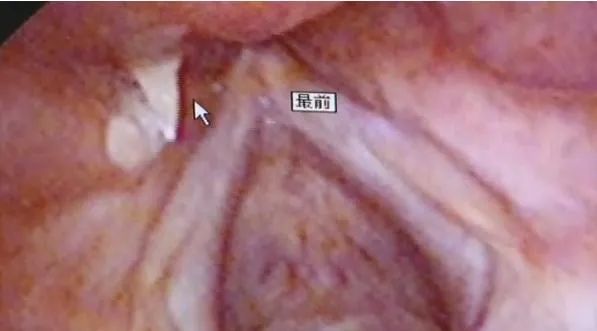

医生通过喉镜检查,竟然在他的喉腔中发现了一根十分隐蔽的鱼刺。更夸张的是据他本人回忆,这根鱼刺大概是半年前就已经“植入”他的身体里了。当时他不小心把鱼刺鲠在舌根下面,以为吞口饭下去就没事了,没想到鱼刺却在吞咽时被挤压到组织下面藏了起来。

这根鱼刺如果掉落进气管中当天他马上就得来医院,神奇的是它刚好就卡在患者的喉部,直到几个月后才引起明显的疼痛。最终通过全麻手术医生取出了这根“寄生”了半年之久的鱼刺,才让患者摆脱了困扰多时的病痛。